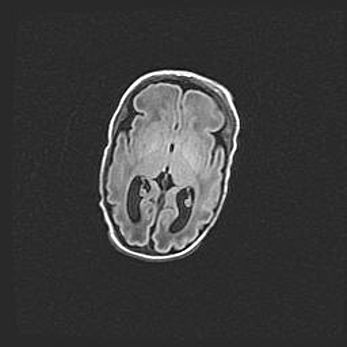

Множественные кисты обоих полушарий головного мозга, наибольшая из них в правой затылочной области. Ассиметричная атрофическая гидроцефалия.

Возраст: 7 месяцев

Вес: 5660 г

Пол: мужской

Окружность головы: 41,5 см

Срок гестации: 28-29 недель

Кисты головного мозга развиваются в результате многоочаговых некрозов вещества мозга и возникают вследствие перенесенной перинатальной инфекции, менингитов, энцефалитов, асфиксии, родовой травмы, расстройств мозгового кровообращения различного генеза. Образованию кист в веществе головного мозга плодов и новорожденных способствуют такие факторы, как высокое содержание в нем воды, недостаточная (или отсутствие) миелинизация и слабая астроглиальная реакция на повреждение.

Кисты могут сочетаться с гидроцефалией и другими поражениями головного мозга.